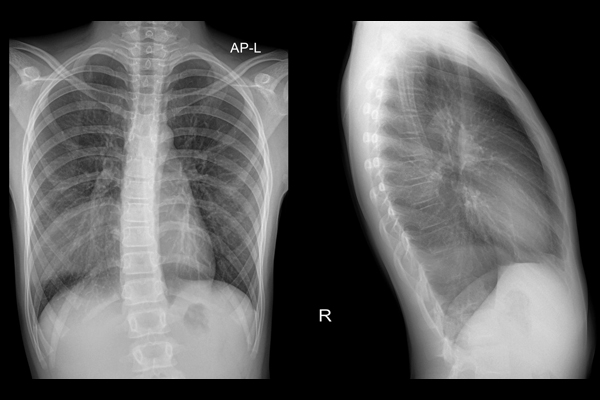

Pneumonia is defined as an infection of the lung tissue, in which the alveoli become filled with micro-organisms, fluid and inflammatory cells, affecting the function of the lungs. Community acquired pneumonia (CAP) has a mortality rate of around 1% in those who are managed in primary care, rising to up to 14% for those admitted to hospital and to 30% for those who need intensive care. GPs need to risk stratify and make logical decisions as to who can be managed in the community, and who needs referral and consideration of admission. In this blog post we discuss the NICE guidance on Antibiotic prescribing changes for pneumonia in children which was launched in September 2025. This course falls within the Respiratory health curriculum field. Production, editorial, and distribution owned by the Royal College of General Practitioners.